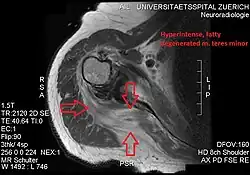

Conjoint and intact tendon disc of teres minor and infraspinatus muscle.

Intact teres minor tendon with physiologically hypointense signal.

Hyperintense, fatty degenerated teres minor muscle.

Ultrasonography is a tool to detect a fatty degenerative atrophy of the teres minor and shows in affected muscles increased echogenicity and betimes a slight reduction in muscle bulk. MR imaging helps to consolidate the diagnosis of neurogenic muscle atrophy. Extracellular edema after traumatic events causing neural damage show an increased signal intensity on T2-weighted MRI sequences and normal intensity on T1-weighted sequences. Posterior humeral circumflex artery compression and reduced blood flow in stressful arm positions and or maneuvers can be diagnosed by a Doppler ultrasonography. The nerve should be detected adjacent to the vessel. In an elevated arm position the axillary neurovascular bundle can be seen at the posterior axillary fold just before it perforates the deltoideus, while the posterior course is well visible in the neutral position. For a detailed assessment of the artery, a MR angiography is required. The major task of an ultrasonographic examination is to rule out any space occupying mass. Additional electromyography is helpful to reveal any decelerated nerve conduction velocity, and thus denervation of the concerned muscle.[6]